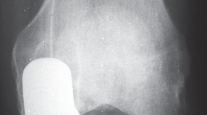

التصوير الطبي ضروري لتأكيد التشخيص وتحديد مدى تلف المفصل:

-

الأشعة السينية العادية (Plain Radiographs):

- المنظر الأمامي الخلفي (AP): يُظهر الركبة من الأمام.

- المنظر الجانبي (Lateral): يُظهر الركبة من الجانب.

- المنظر الخلفي الأمامي المثني (PA Flexed): يسمح بتقييم أفضل للجزء الخلفي من الركبة وقد يكشف عن تغيرات أكبر في الحجرة الخلفية الوحشية.

- منظر شروق الشمس (Sunrise/Patellofemoral): لتقييم المفصل الرضفي الفخذي.

- الأشعة السينية الطويلة للطرف السفلي بالكامل (Full-length standing radiographs): من الورك إلى الكاحل، وهي مفيدة جدًا، خاصة إذا تم استخدام تقنيات الملاحة الحاسوبية. تُظهر هذه الأشعة المحاذاة الكلية للطرف السفلي.

التصوير بالرنين المغناطيسي (MRI): يُعد ضروريًا في حالات التنخر العظمي لاستبعاد إصابة الحجرات الأخرى.